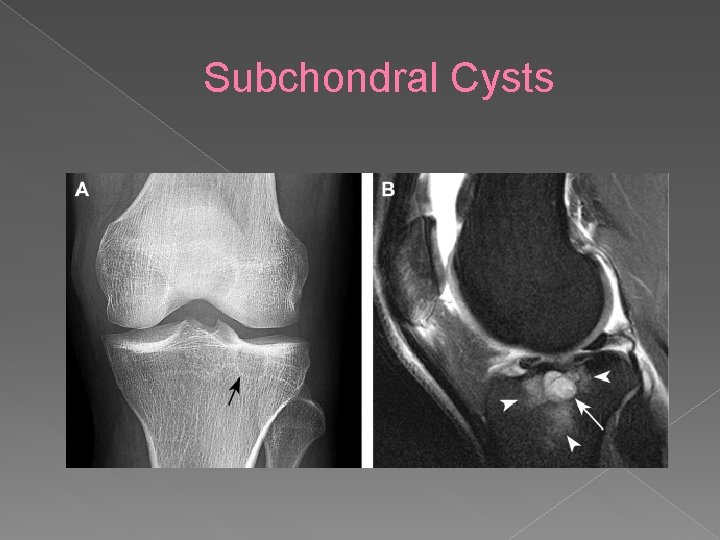

Subchondral Cysts